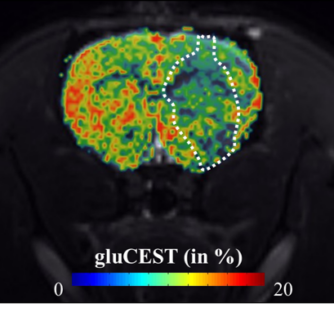

Imaging astrocyte reactivity using GluCEST MRI